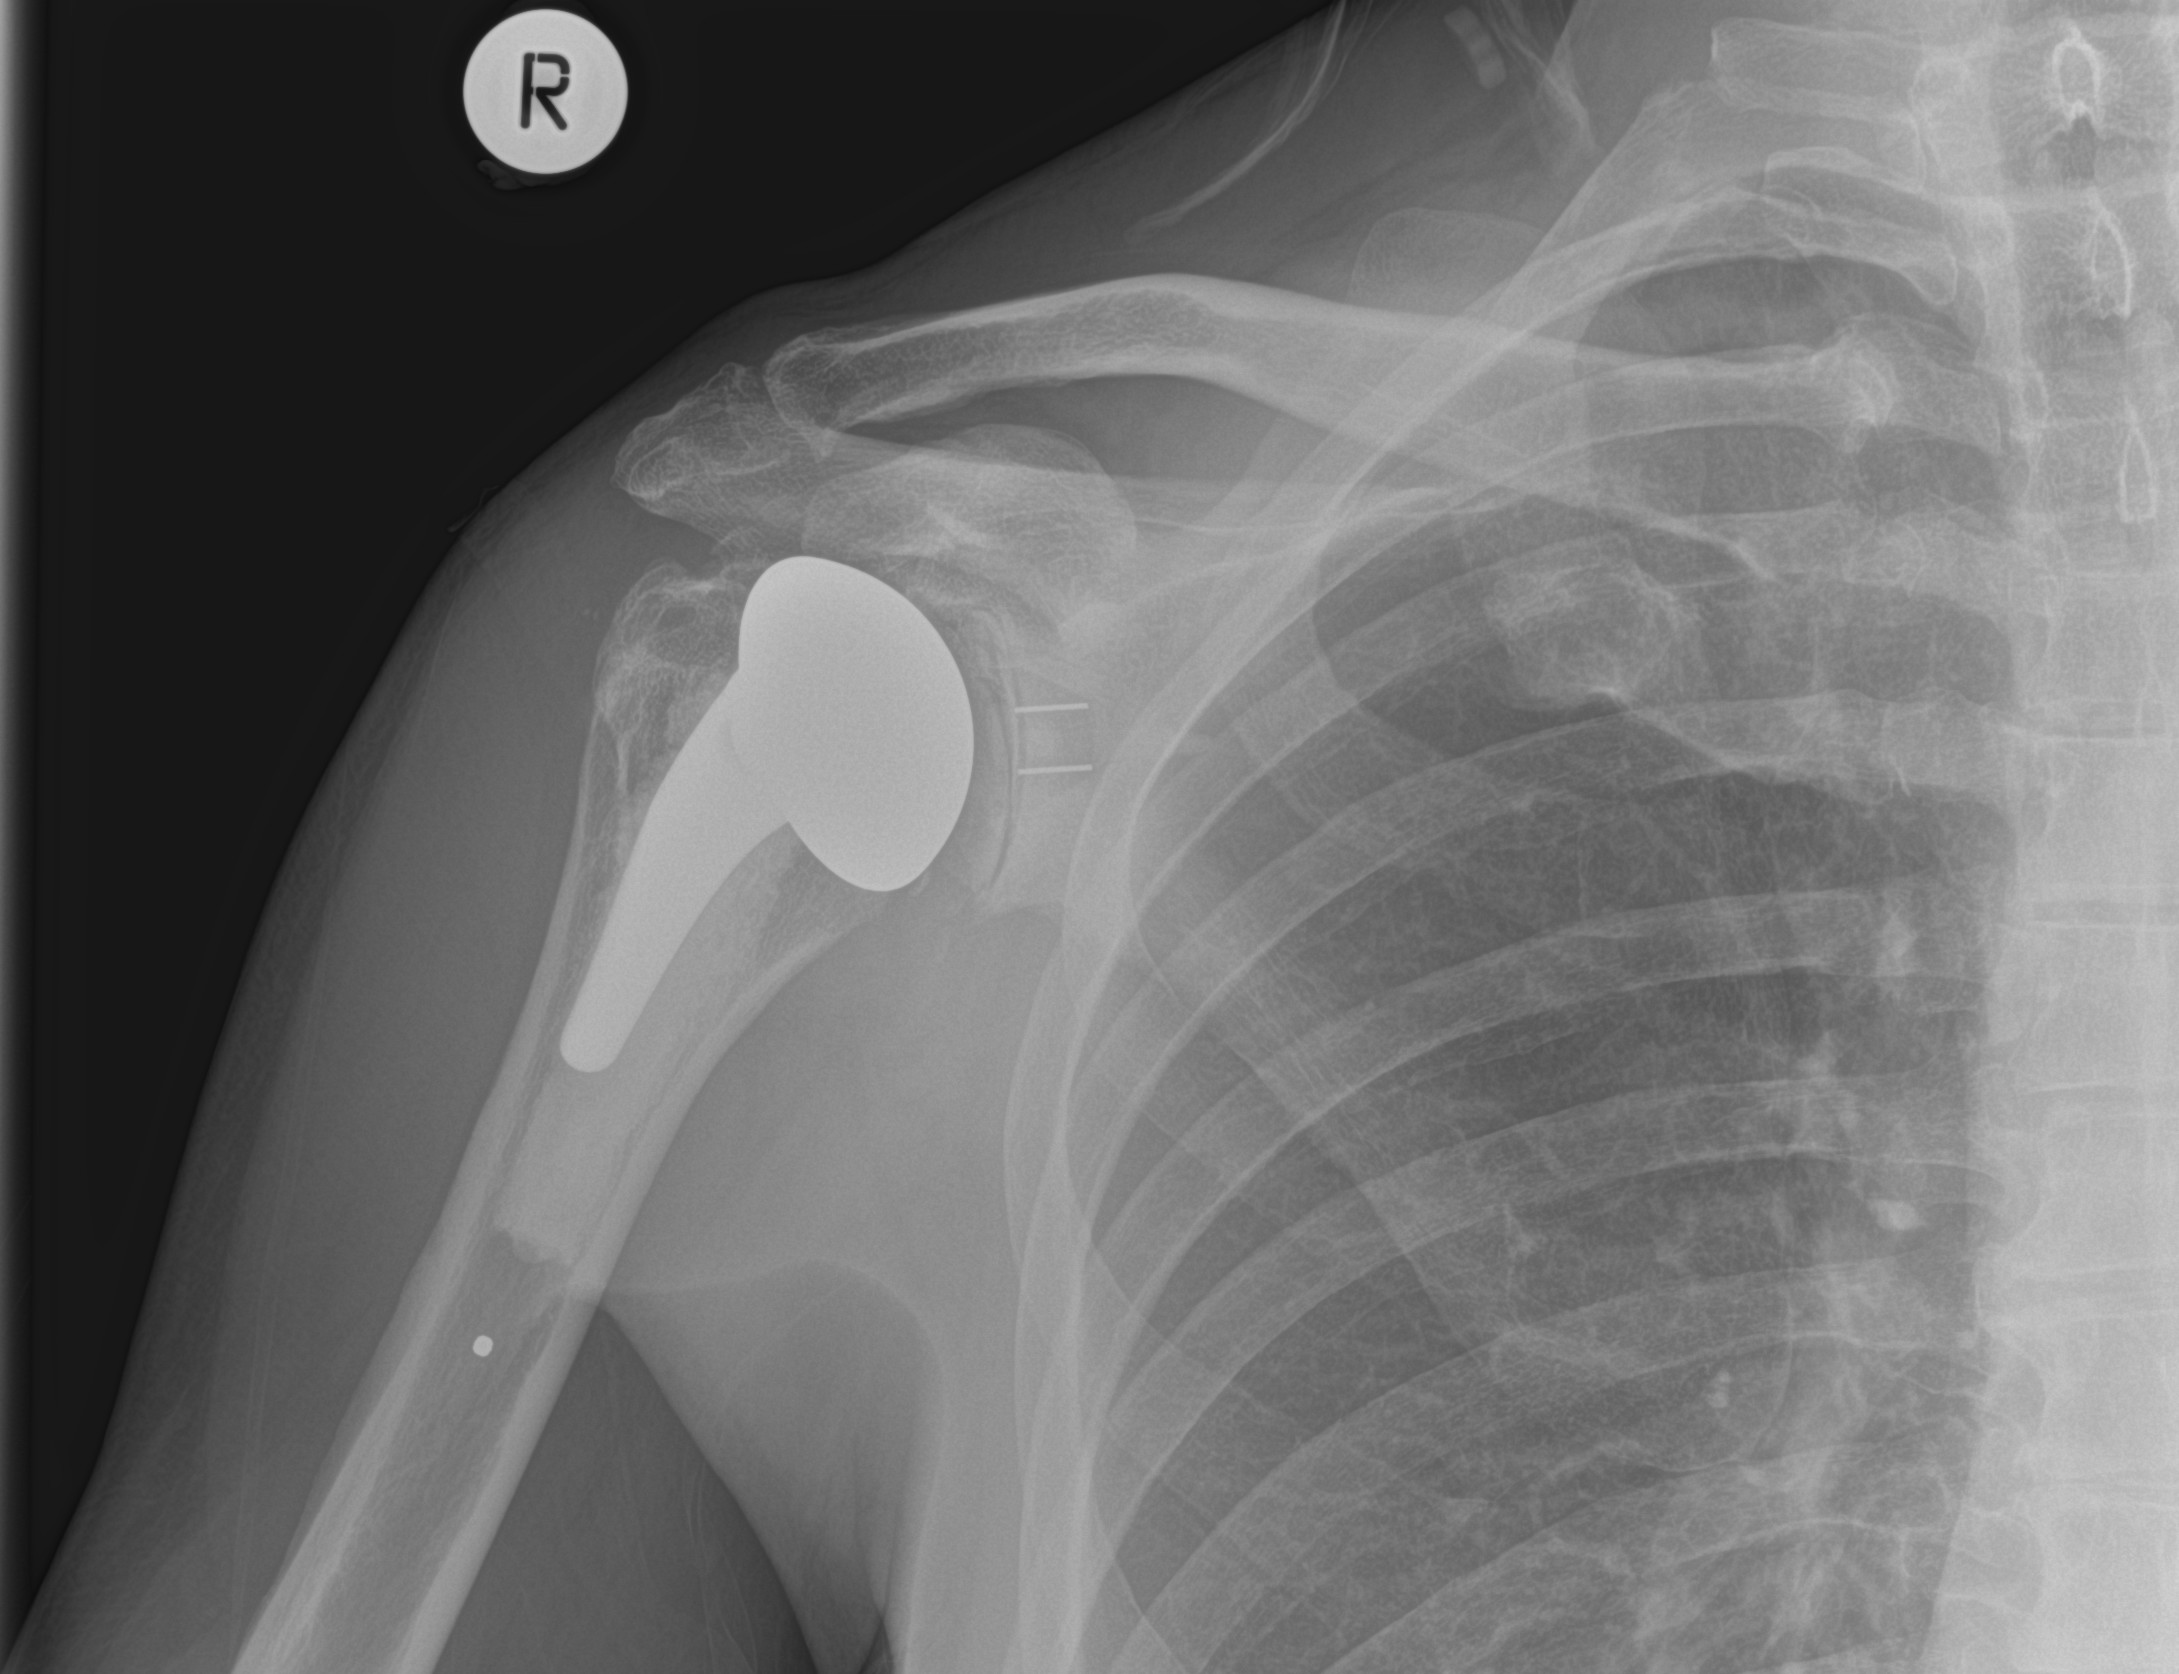

However, the purpose of my visit was for a 9 month check on ‘the shoulder’. And my shoulder man moved to this hospital mid-way through my time with him. It’s him I want to see. Because I love him dearly. Like a father. A son. The step-sister I never had. Whatever. And I don’t care where he happens to be, I’ll go there. Because he saved me. From a life without tennis. Or ever scratching my arse with my right hand again. And this is what my shoulder now looks like. This ‘selfie’ was taken yesterday, which is why my arm looks a bit older than on the one they took back in February.